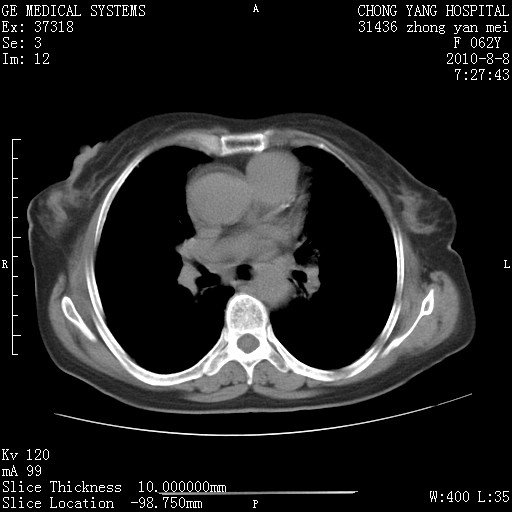

标题: CT28269:F62Y咳嗽胸痛数月。 [打印本页]

标题: CT28269:F62Y咳嗽胸痛数月。

1.肺间质纤维化.

2.纵隔淋巴结肿大。

3.迷走右锁骨下动脉。

两肺间质改变,纵隔淋巴结肿大,需要考虑结节病的可能。